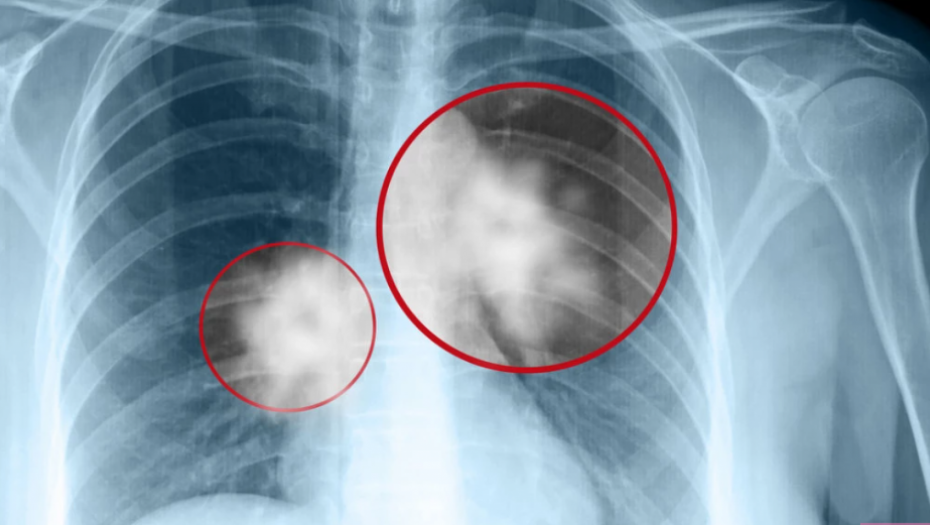

"Plućna hipertenzija je bolest krvnih sudova u plućima, teška, progresivna, vrlo opasna i nezgodna bolest koju nije lako prepoznati. Obično kreće zamaranjem u naporu, osećajem nedostatka vazduha u naporu, to tako potraje nekoliko meseci dok se pacijenti jave sa ovim tegobama, a takvim tegobama može nažalost da počne i više desetina, ako ne i više stotina što plućnih, što srčanih oboljenja".

"Već na ultrazvučnom pregledu se jasno vidi da su uvećane desne srčane šupljine, da su prošireni krvni sudovi u plućima, da su povišeni pritisci i da zapravo razlog za zamaranje nije ni u čijoj glavi već je organski problem – zadebljani su zidovi krvnih sudova, postoji ugrušak koji se zaglavio u nekim od krvnih sudova u plućima... Ti povišeni pritisci zapravo opterećuju desnu stranu srca koja nije predviđena da radi pod visokim pritiscima. Leva polovina srca radi pod pritiskom koji je idealan, što se gornjeg pritiska tiče između 120 i 135, a desna polovina srca ima nekoliko puta niži pritisak i treba da bude ispod 25 srednji pritisak u plućima, ispod 30 gornji".

Kardiolog je objasnio da ukoliko je desna polovina srca dugo izložena visokom pritisku počinje da se širi, zidovi slabe i razvija se progresivna srčana slabost.